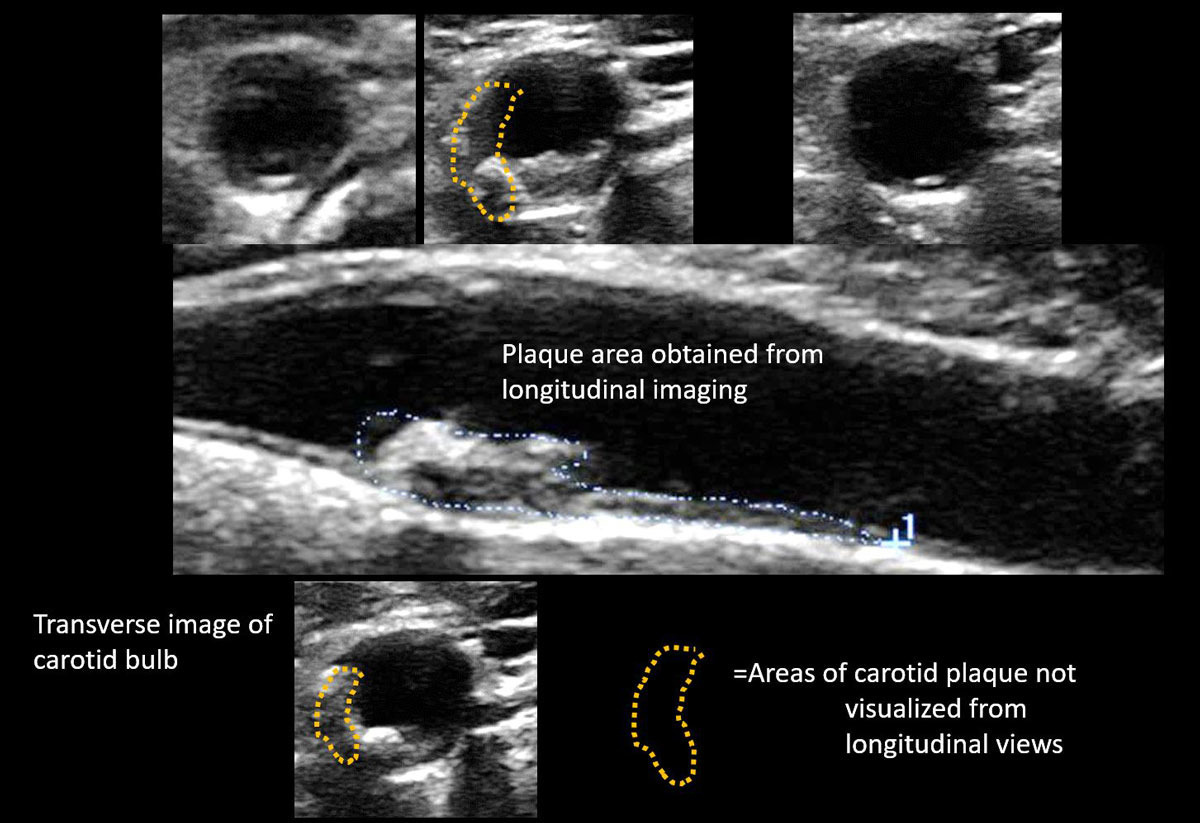

2. 죽상동맥경화증(Atherosclerosis)

- 혈관벽에 지방 찌꺼기(죽종, plaque)가 축적되어 탄력을 잃고 혈류를 방해하는 상태입니다.

5. 혈관 노화 지표

- 내중막 두께(IMT) 측정으로 혈관 노화 정도를 정량화할 수 있습니다.

- 의사가 협착 정도 및 IMT 수치, 혈류 이상 등을 설명